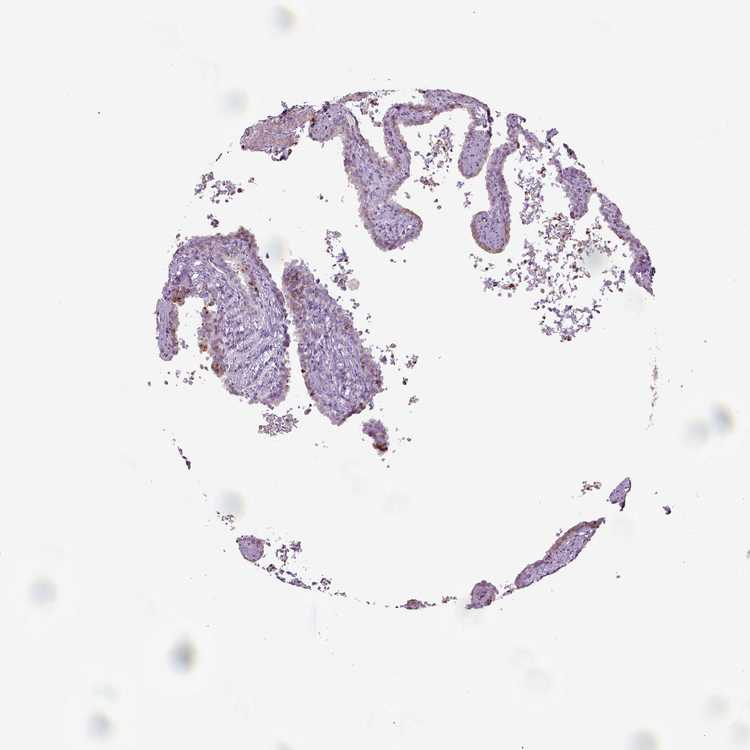

TISSUE PRIMARY DATA SEMINAL VESICLE Show tissue menu

SEMINAL VESICLE - Antibody stainingi

Antibody staining in the annotated cell types in the current human tissue is reported as not detected, low, medium, or high, based on conventional immunohistochemistry profiling in selected tissues. This score is based on the combination of the staining intensity and fraction of stained cells.

Each image is clickable and will lead to virtual microscopy that enables deeper exploration of all samples and also displays staining intensity scores, fraction scores and subcellular localization as well as patient and tissue information for each sample.

Antibody HPA062937Antibody CAB012993

Glandular cells Not detectedMedium